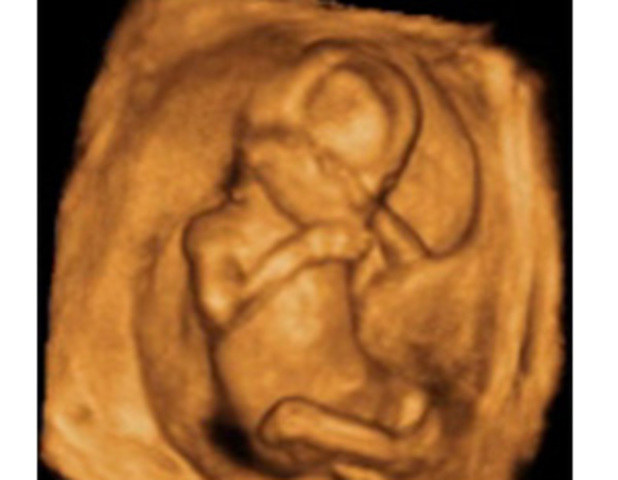

• SEMANA 25

SEMANA 25

Pesa ya 700 gramos y mide 22 centímetros desde la cabeza al final de la columna ( cráneo-caudal).

Los párpados del niño se abren y se pueden ver los ojos. La lengua sale de la boca y se mueve hacia los lados. Tu hijo bosteza, sonríe y empieza a hacer gestos como si de un niño mayor se tratase